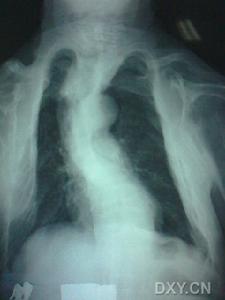

X線胸片多數雞胸不像漏斗胸那樣在出生後即能發現,往往在五、六歲以後才逐漸被注意到。一般雞胸很少發生壓迫心肺的症狀,重症雞胸常出現反覆上呼吸道感染及支氣管喘息,活動耐力較差,易疲勞。更主要的是患者因畸形而在精神上有極大的負擔。

(1)X線:胸部X線顯示胸骨下部和相鄰肋軟骨明顯下陷,脊柱與胸骨間距增加。脊柱X線觀察脊柱有無側彎等。

主要為胸骨伸長、向前凸起、雙側下份肋軟骨下陷,狀若船的龍骨,嚴重者使胸腔容量減小。側位X線片上見肋骨與胸骨分離,胸骨後間隙延長。

球形鴿胸的特徵為胸骨柄、胸骨體連線處與相鄰肋軟骨的隆起,若有胸骨角(louisangle)的減小,則會造成胸骨體下2ö3的下陷,使第2至第5肋軟骨在胸骨旁隆起。球形鴿胸常伴有胸骨骨化線,特別是胸骨柄、胸骨體連線處的早期骨化,在患兒3歲、甚至3歲以前即可看到。而在一般情況下,99%的人不管年齡如何,其胸骨柄、胸骨體連線處是開放的[5]。胸骨柄與體連線處的骨化和胸骨角的隆起,稱為“胸骨成角性骨連線”(angulatedsynostosisofthesternum)。